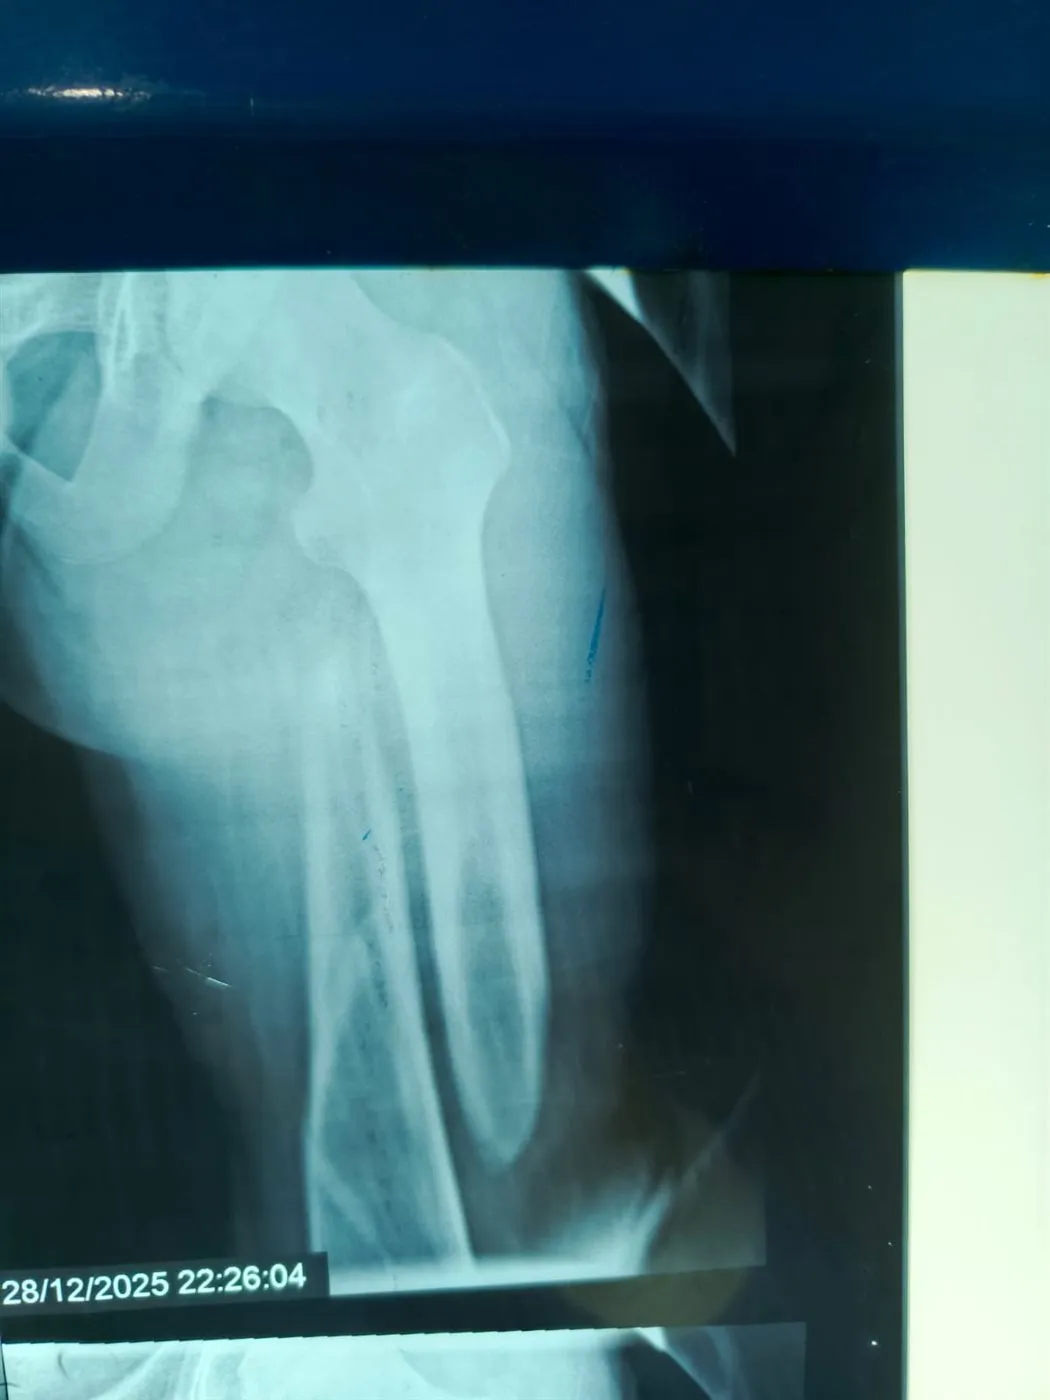

نجح الفريق الطبي بقسم الطوارئ والعمليات بمستشفى مغاغة العام بمحافظة المنيا، في إنقاذ شاب يبلغ من العمر 16 عامًا، تعرض لحادث مروري مروع أسفر عن كسر مفتت متعدد المواضع بعظمة الفخذ الأيسر، وذلك من خلال إجراء جراحة متقدمة باستخدام تقنية المسمار النخاعي التشابكي في زمن قياسي.

وفور وصول المصاب إلى قسم الطوارئ، جرى التعامل الفوري معه، وتم اتخاذ القرار الطبي العاجل بإجراء جراحة المسمار النخاعي التشابكي دون فتح موضع الكسر، بما يتوافق مع أحدث البروتوكولات الطبية العالمية. واستغرقت العملية نحو ساعتين ونصف فقط، غادر بعدها المريض غرفة العمليات في حالة مستقرة.